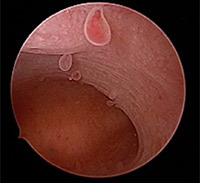

εικόνα μικροκυστικων πολυπόδων

- για την ποιότητα του ενδομητρίου,

Εικόνα ενδομητρικού πολύποδα